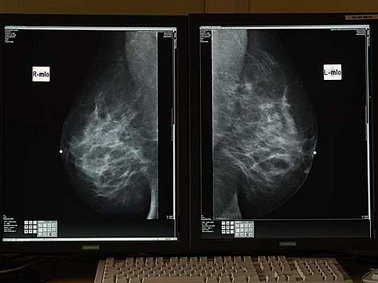

Digitale Mammografie

Die Mammografie ist die Röntgenuntersuchung der weiblichen Brust. Auch dies wird in digitaler Technik durchgeführt zur besseren Kontrastierung und Strahlenreduktion. In unserer Praxis wird nur die klinische Mammografie durchgeführt. Dies bedeutet, dass wir nicht am sogenannten Mammografiescreening teilnehmen, sondern nur Patientinnen auf Überweisung, bei denen ein unklarer Tastbefund, unklarer Ultraschallbefund, einseitige Schmerzen oder eine positive Familienanamnese (Brustkrebs bei engen Verwandten) vorliegt. Privat versicherte Patientinnen können bei vorliegender Indikation selbstverständlich auch ohne Überweisung untersucht werden.

Die klinische Mammografie umfasst im Gegensatz zum Screening ein Arztgespräch und gegebenenfalls auch sofort die ergänzende Ultraschalluntersuchung, wenn erforderlich.